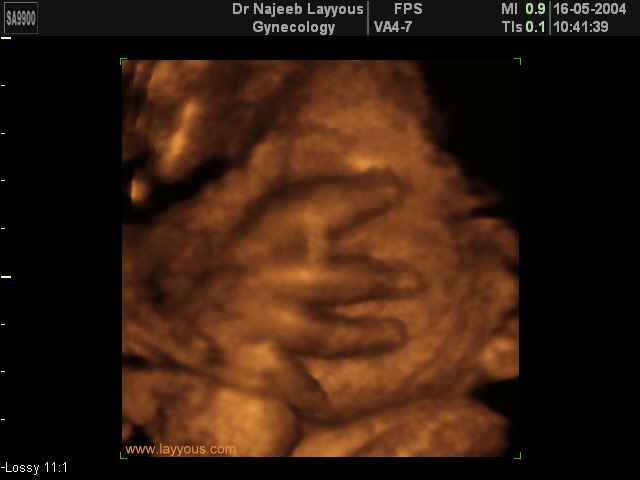

- صور لأطراف الجنين

- صور لتصرفات الجنين داخل الرحم

صور لأطراف الجنين بجهاز الالتراساوند ثلاثي الأبعاد | الدكتور نجيب ليوس